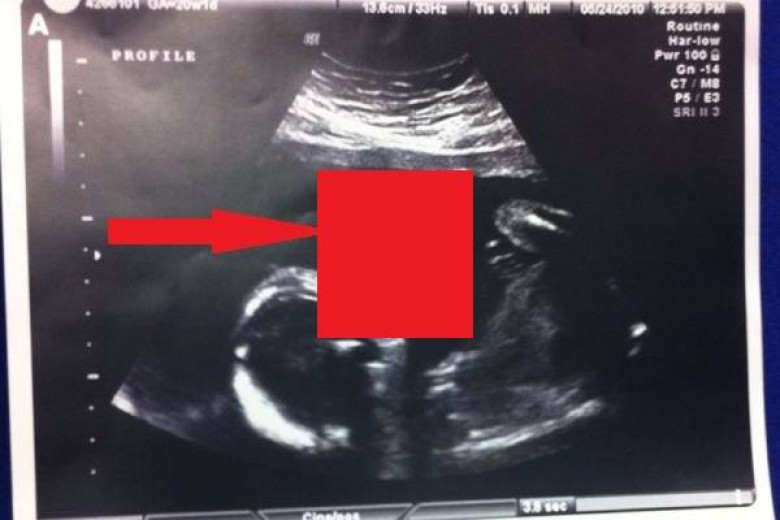

LifestyleТамми Гонзалес из США была на 17 неделе беременности, когда врачи обнаружили нечто необычное вовремя очередного сеанса УЗИ. Казалось, будто малыш в утробе надувает пузырь. Увиденное, как бы там ни было, оказалось тератомой, редкой разновидностью раковой опухоли. Врачи рекомендовали Тамми немедленно провести операцию по удалению образования, пока малыш еще находится в утробе. Иначе девушка могла потерять ребенка.